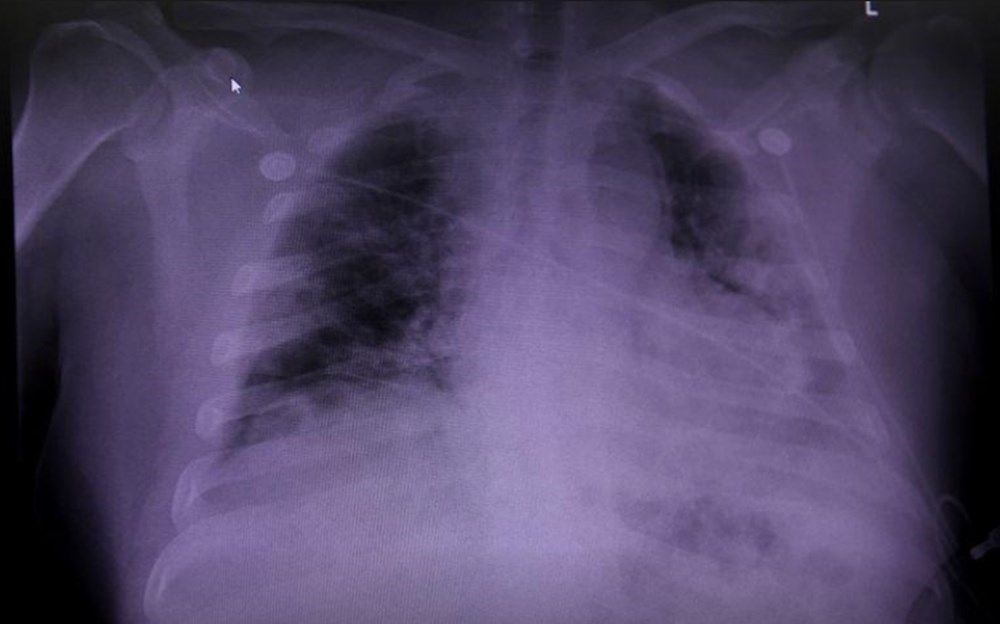

Bununla birlikte, araştırmacılar taramaya tabi tutulan ilk 200 kişiden alınan ön verilerde, hastaların yaklaşık yüzde 70’inin Covid-19’a ilk kez yakalandıktan dört ay sonra kalp, akciğerler, karaciğer ve pankreas dahil olmak üzere bir veya daha fazla organlarında çeşitli hasarlar meydana geldiği açıkladı.

Öte yandan araştırmada, deneklerin bazılarında, semptomlar ile organ hasarının yeri arasında doğrudan bir ilişki olduğu görüldü. Örneğin, kalp veya akciğer bozuklukları nefes darlığı ile ilişkiliyken, karaciğer veya pankreas bozuklukları gastrointestinal semptomlarla bağlantılıydı.

Geçen hafta Imperial College of London tarafından yapılan farklı bir çalışmada ise benzer şekilde enfeksiyondan iki ile üç ay sonra, Covid-19 nedeniyle hastaneye yatırılan kişilerin yüzde 60’ının akciğerlerinde, yüzde 29’sunun böbreklerinde, yüzde 10’unun karaciğerlerinde ve bir kısmının beyninde doku değişikliklerine rastlandı.